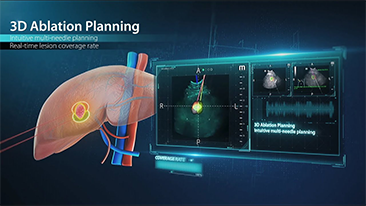

Hoe duidelijk is een lever te zien?

Bij focale leverlaesies, zoals hemangioom of leverkanker, speelt ultrasone contrastbeeldvorming een belangrijke rol. Ultrabrede niet-lineaire UWN+ contrastbeeldvormingstechnologie kan helpen bij het verkrijgen van een betere penetratie, een hogere contrast-weefselverhouding, met een lagere MI en een langere observatie van de perfusietijd.